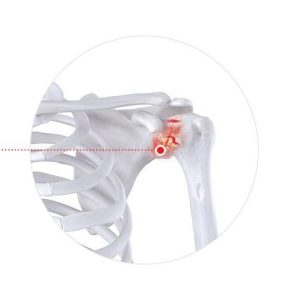

Мөрний булчингийн урагдал

Мөрийг тогтоож байдаг 4 ширхэг шөрмөс нь урагдсанаар гараа нурууны ар тал руу өргөхөд хүчтэй өвдөлт болон мөрөнд ямар нэгэн юм тээглэсэн мэдрэмж төрөхийг мөрний өвчин гэж буруугаар ойлгох тохиолдол элбэг.